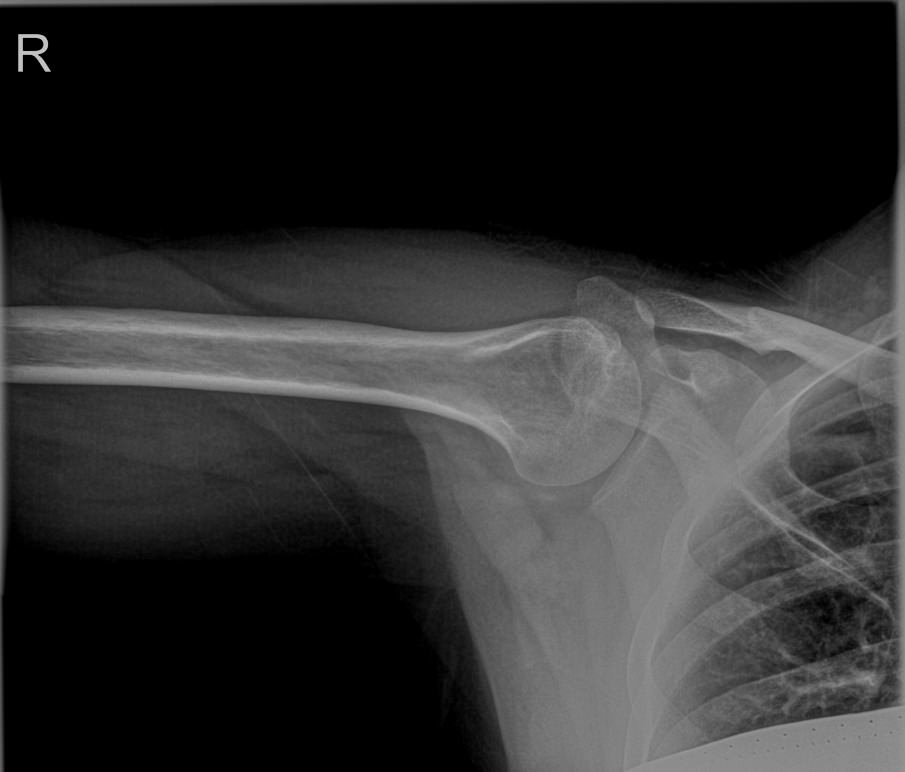

Плечевая кость ― одна из самых крепких в организме, что для ее повреждения требуется удар значительной силы. Переломы могут сопровождаться вывихами плечевого и локтевого суставов. Давно залеченная травма при неблагоприятных обстоятельствах может вызвать прерождение костной ткани.

Во всех случаях первичным методом диагностики будет рентгенография. Это простая и информативная процедура, которая не добавляет неприятных ощущений и быстро показывает полную картину патологии. Современное оборудование, которое используется в клинике «Доступная медицина», позволяет делать несколько снимков в течение короткого времени без опасности чрезмерного облучения.

Что покажет рентген плечевой кости

• Травматические повреждения, в том числе зажившие;

• Формирование костной мозоли;

• Патологические изменения костной ткани: разрежение, некроз, деструкция и другие;

• Состояние смежных суставов, вошедших в снимок;

• Опухоли и метастазы.